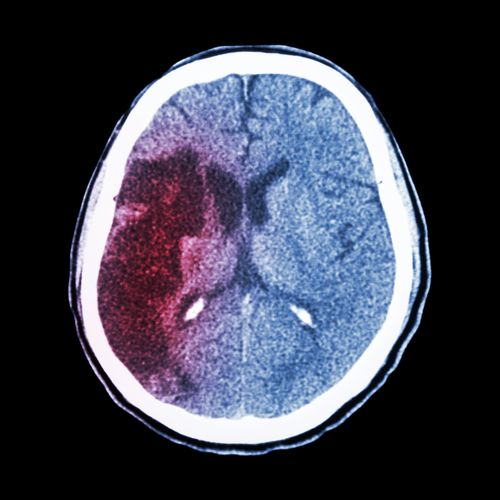

Xarelto accused of causing cerebral hemorrhageTaking the blood thinning medication Xarelto? Take care not to slip and fall, as Xarelto may increase the risk of cerebral hemorrhage in patients who are taking Xarelto and hit their head in a fall.

A cerebral hemorrhage is a type of stroke. The hemorrhage occurs when an artery in the brain bursts and causes bleeding in the surrounding tissue. Cerebral hemorrhage is a serious condition that requires medical treatment. In some cases, the cerebral hemorrhage can lead to death.

Persons taking Xarelto who fall and hit their head may be at risk of developing a cerebral hemorrhage or internal brain bleeding.

Patients who experience a cerebral hemorrhage generally require emergency brain surgery to relieve the pressure that builds up in the skull. The surgery requires drilling a small hole in the patient’s skull to drain the blood.

If the patient survives the initial cerebral hemorrhage, brain bleed recovery may take several months. Brain bleed recovery efforts generally require physical, occupational, and speech therapy. Some patients recover completely while others may have residual problems such as seizures, headaches, or memory problems. While many patients do survive a brain hemorrhage, survival rates decrease when the bleed occurs in certain areas or if the initial bleeding is very large.